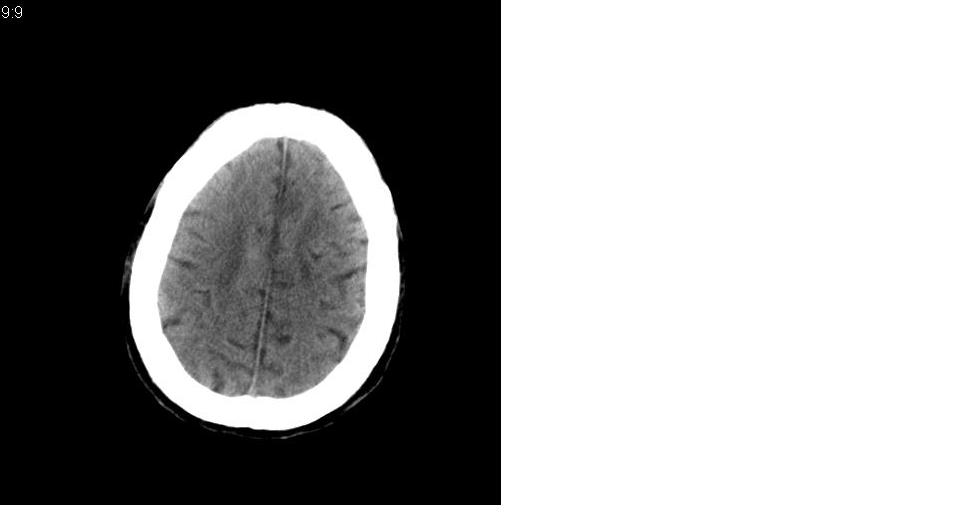

男 73岁,肢体活动不灵多年。

左右侧脑室前后角对称性低密度区,边缘模糊,脑沟,脑池增宽,脑室扩大,左侧基底结区见多个低密度病灶

诊断:1皮层下动脉硬化性脑病

2左侧基底结区腔梗

1.皮层下动脉硬化性脑病 .

2.左基底节区梗塞软化灶。